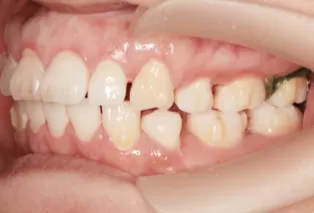

Photos intra-orales